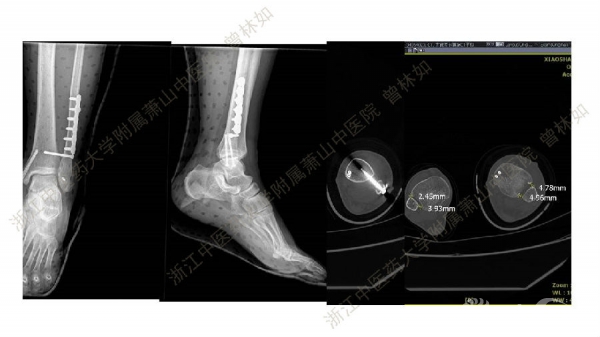

2017-06-13 文章来源:浙江中医药大学附属萧山中医院 作者:曾林如 我要说